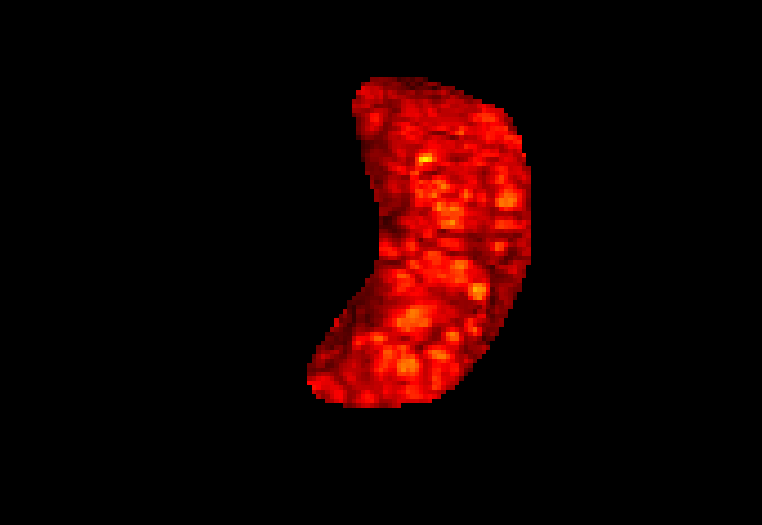

This atlas and the linked publication [1] aim to give a visual overview over T2-weighted anatomical imaging and T2* relaxometry placental data. Both have been widely used in the last years to assess placental structure and function in-vivo [2-10].

Data from healthy controls is displayed over GA, different acquisition choices and possible dynamic effects are depicted and placentae from different cohorts affected by complications are shown.

Display description: All placentae are shown in maternal coronal plane (See A). The slice with the largest placental volume was chosen. The same colormap was chosen for all placentae (See B).